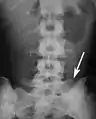

تقطّن الفقرات العجزية، ويظهر كست فقرات لا تتصل بالضلوع.

تعجُّز الفقرة القطنية الخامسة ويظهر في أسفل يمين الصورة.